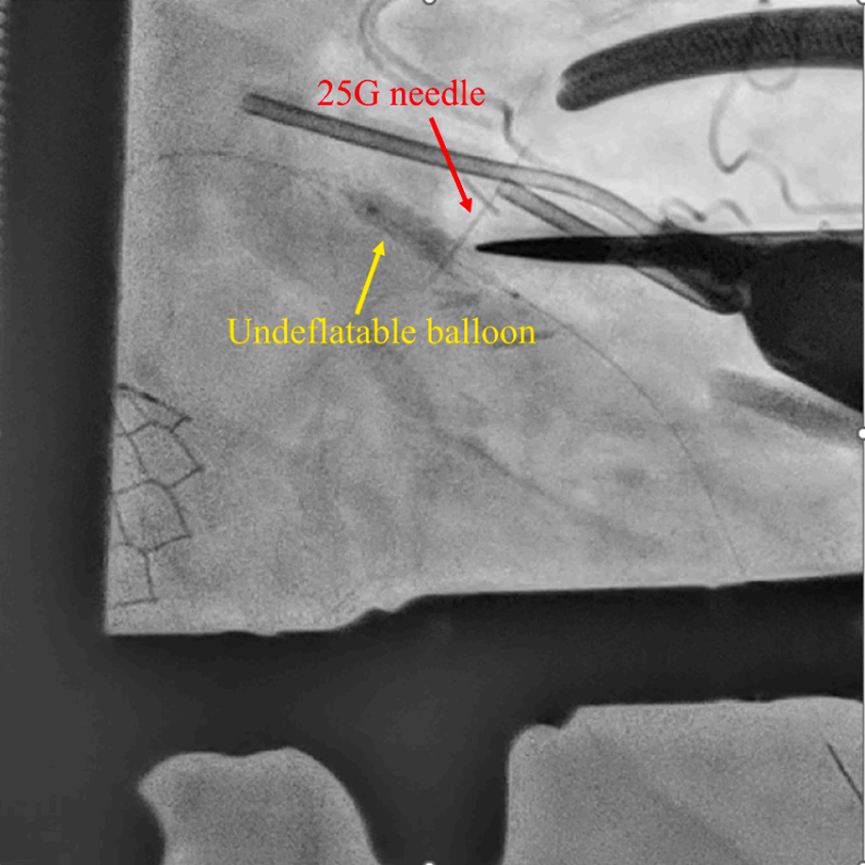

鉴于患者心电图ST段持续抬高,进一步的经皮导管手段已无能为力,于是紧急决定实施外科手术取出球囊。在全身麻醉下,于左前胸开约3 cm的小切口进胸,直视下显露心脏左前降支。在透视引导下确定球囊在冠脉内的位置后,使用一根25G的细针从冠状动脉表面穿刺刺入球囊(图2)。

图2